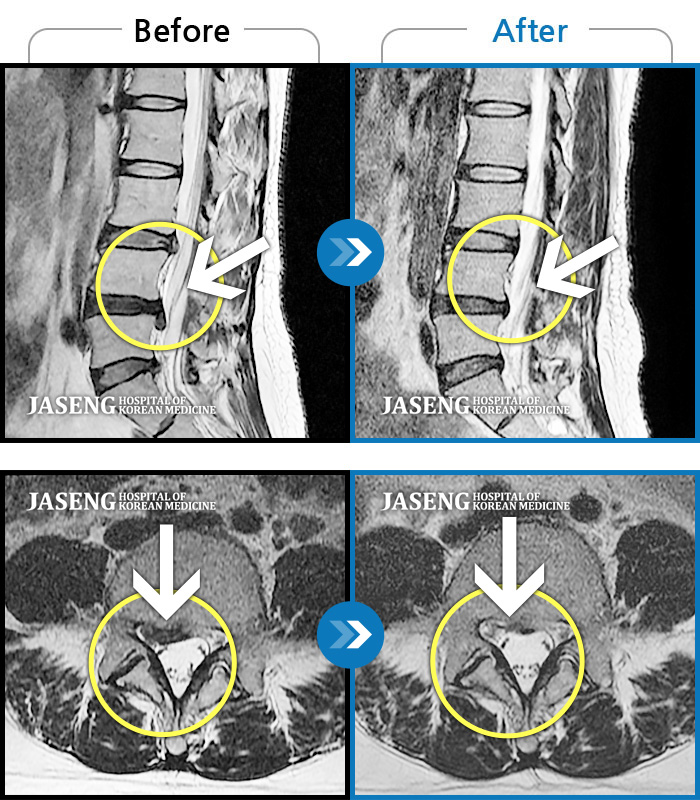

허리디스크

도움받은 사례

인천 · 조남훈 원장

재채기 하고 나서 다리에 힘이 안들어가요.

촬영시기

2021.11.10 ~ 2024.11.26

2024.12.04

조회수 443